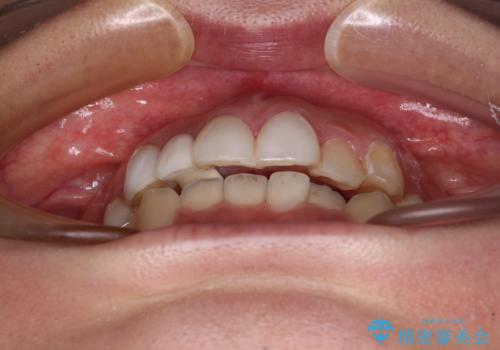

前歯のデコボコが気になる インビザラインによる矯正治療

- 上下前歯のデコボコを気にして来院された患者様です。

インビザラインによる上下歯列の拡大と、IPR(歯と歯の間を削る)にるスペースの獲得により、前歯のデコボコを改善することとしました。